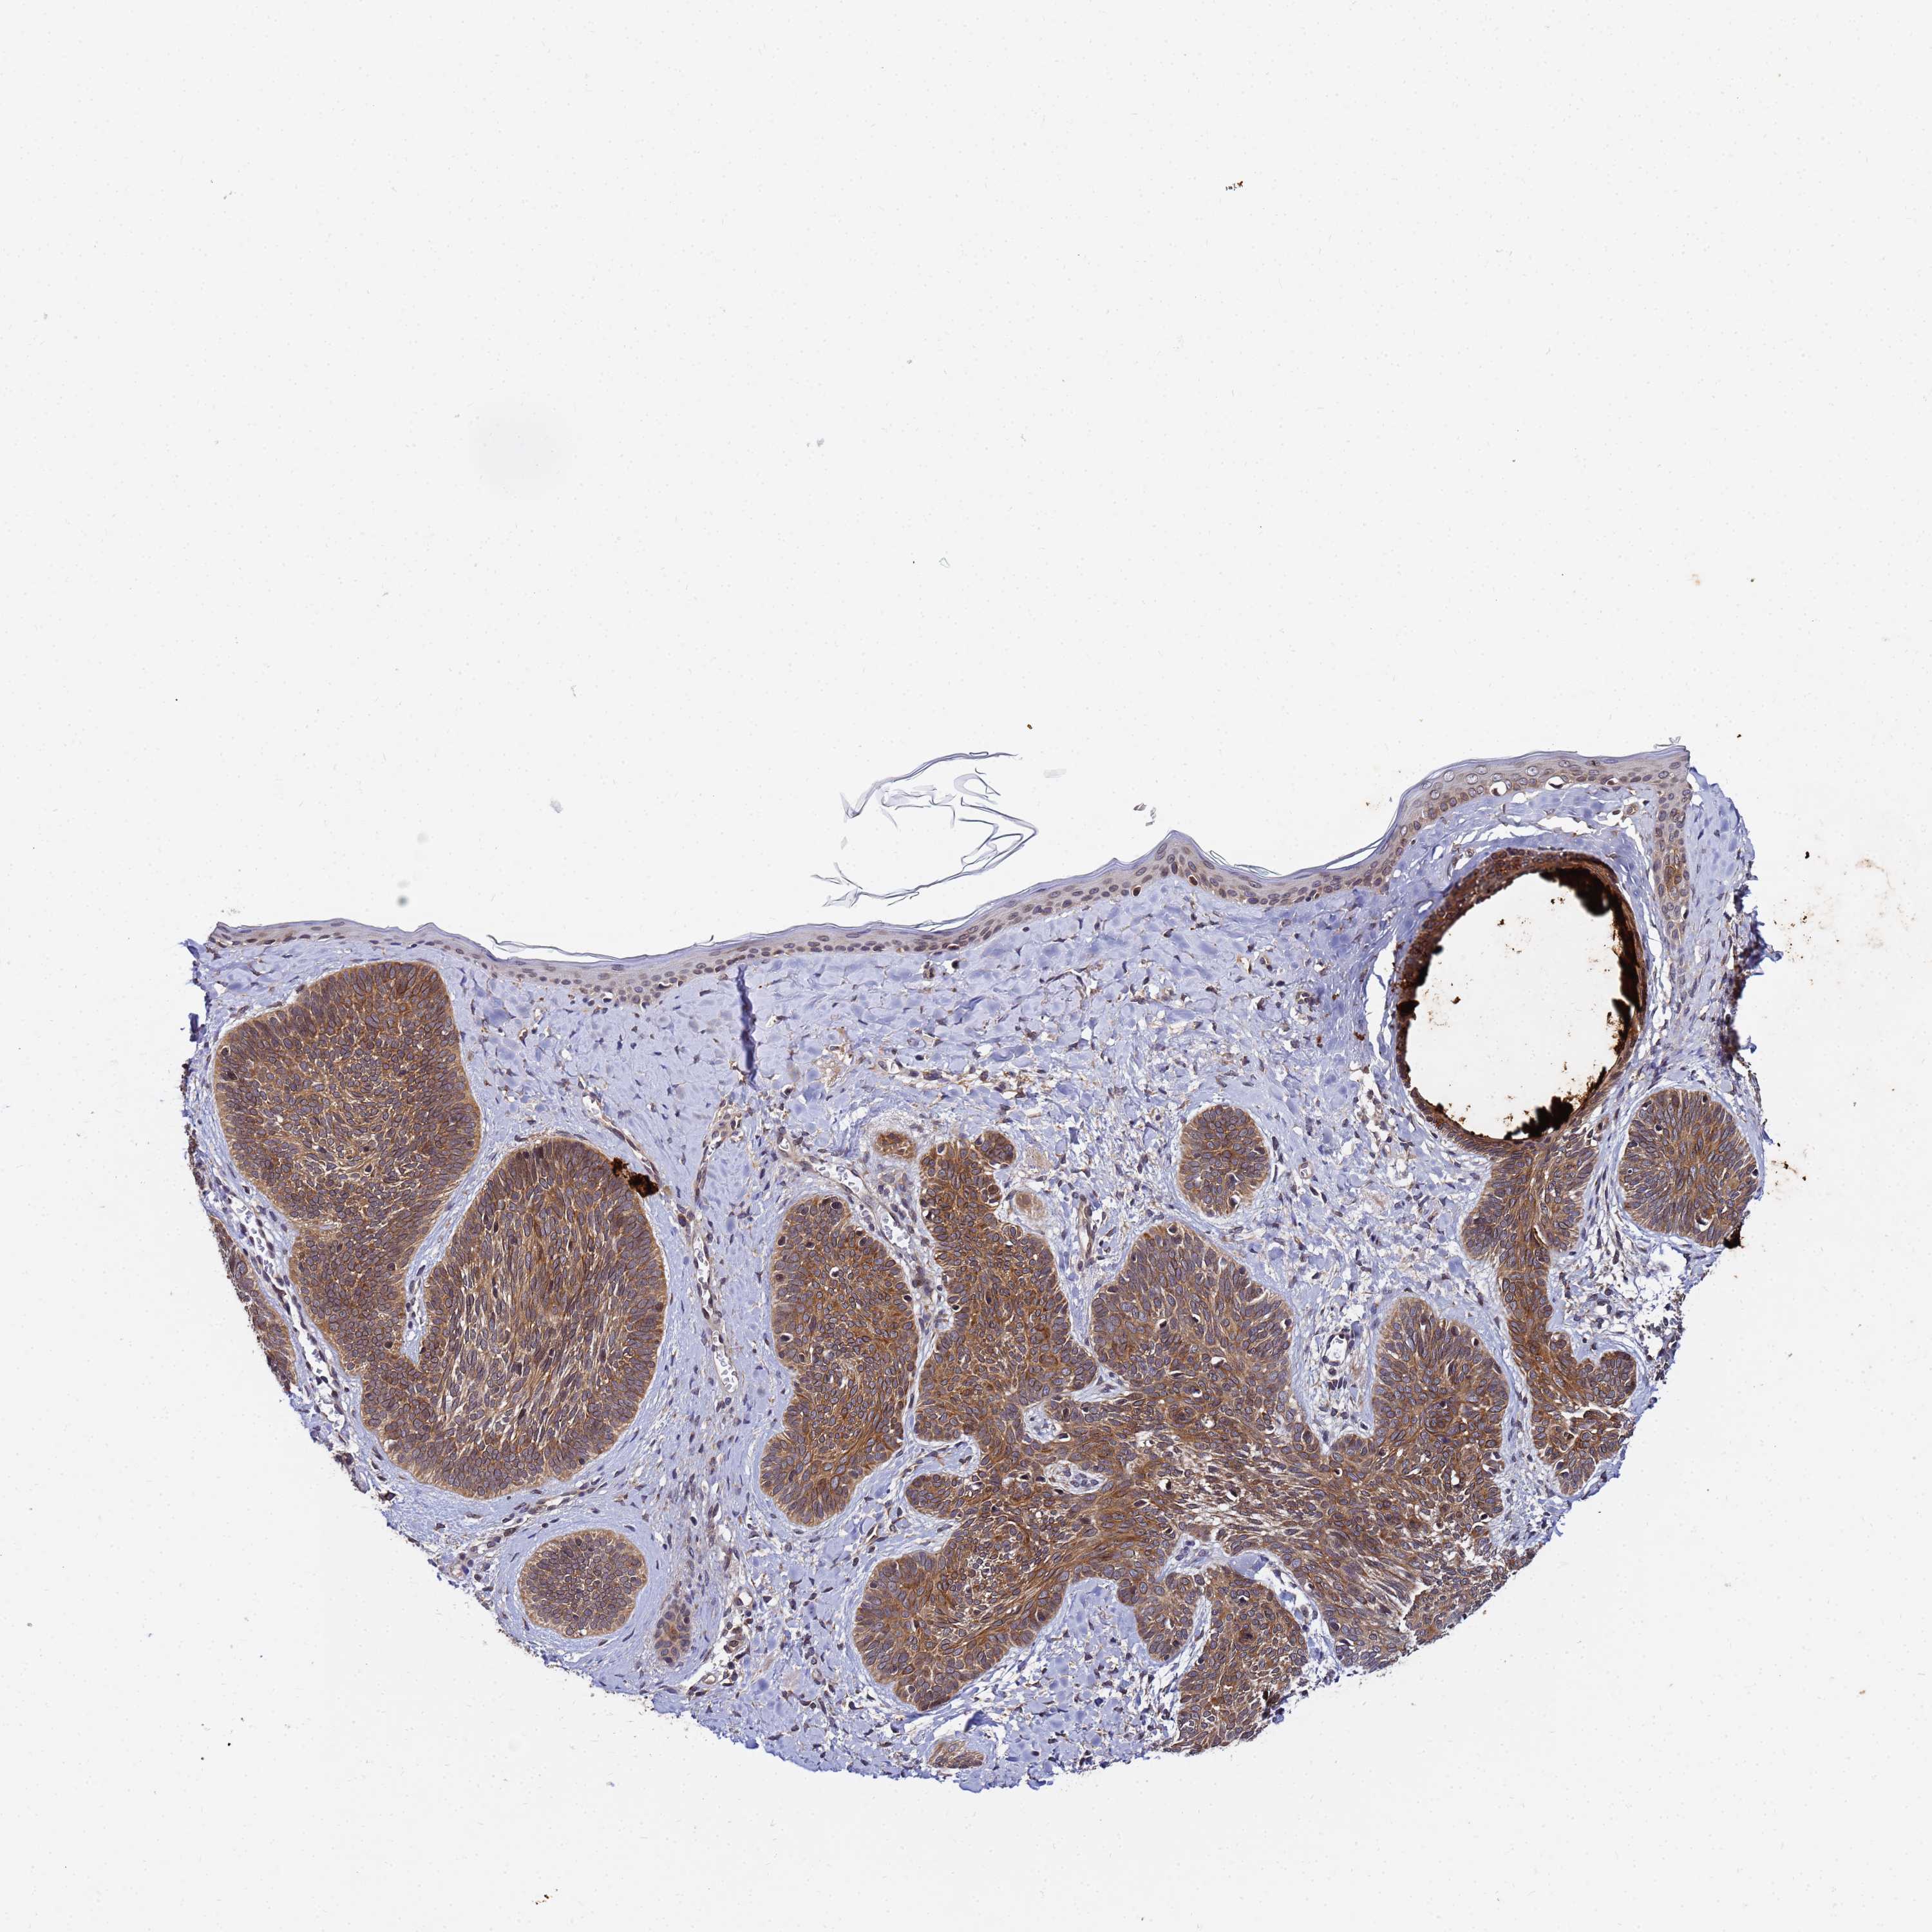

SKIN CANCER - Protein expressioni

A mouse-over function shows sample information and annotation data. Click on an image to view it in a full screen mode. Samples can be filtered based on level of antibody staining by selecting one or several of the following categories: high, medium, low and not detected. The assay and annotation is described here.

Antibody staining in the annotated cell types in the current human tissue is reported as not detected, low, medium, or high, based on conventional immunohistochemistry profiling in selected tissues. This score is based on the combination of the staining intensity and fraction of stained cells.

Each image is clickable and will lead to virtual microscopy that enables deeper exploration of all samples and also displays staining intensity scores, fraction scores and subcellular localization as well as patient and tissue information for each sample.

Antibody HPA042803

Squamous cell carcinoma, NOS